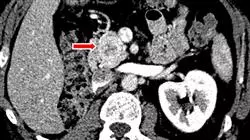

Die ständigen wissenschaftlichen Fortschritte haben zur Entwicklung moderner diagnostischer und therapeutischer Methoden geführt, die darauf abzielen, das Leben von Patienten mit Leber-, Bauchspeicheldrüsen- oder Gallentumoren zu erhalten. In diesem Zusammenhang wird die mögliche Wirksamkeit von Tests wie DCP, Glypican-3 oder Osteopontin zur Förderung der Früherkennung sowie die Entwicklung neuartiger adjuvanter Therapien zur Minimierung des Risikos eines Wiederauftretens von Krebs nach der Operation ständig untersucht. Diese zahllosen Fortschritte sind ein hervorragender Verbündeter für das Wohlergehen der Menschen, die von diesen Krankheiten betroffen sind, und zwingen die Ärzte, sie zu erkennen, um an der Spitze ihres Fachgebiets zu stehen.

Vor diesem Hintergrund hat TECH diesen universitätskurs konzipiert, in dem der Spezialist die neuesten Innovationen in der Behandlung von Pankreas-, Gallen- und Lebertumoren kennenlernt. Während dieser akademischen Periode werden sie die diagnostischen Fortschritte zur Bestimmung der Resektabilität von Bauchspeicheldrüsenkrebs oder die aktualisierten Behandlungen der adjuvanten und neoadjuvanten Strahlentherapie für diese Krankheit erkennen. Sie werden auch in der Lage sein, neue Entwicklungen in der Behandlung von Patienten mit Cholangiokarzinom und Gallenblasenkrebs oder im jeweiligen Ansatz zur Lebertransplantation bei hepatozellulärem Karzinom zu erkennen.